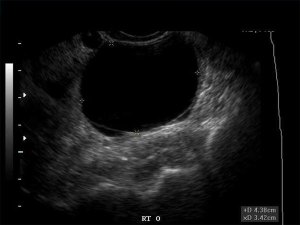

This is a photo of an ovarian cyst. It’s not mine, but it is exactly like the image I saw today while lying sprawled quite uncomfortably on the examination table. I have been having cramps pretty much all the time and passed it off as anxiety, but then some abnormal bleeding showed up. So I went to the doctor. I nearly came up off the table during the very embarrassing exam because the pain was so severe.

The sonogram showed that my cyst is filled with fluid. It has no blood flow.

There is no treatment at the stage in the game unless it does not go away on its own or gets significantly larger. I have to say, it is disconcerting to walk around knowing I have a 4-cm balloon on the side of my ovary that could rupture (causing severe pain) at any moment. But it is also comforting to know that I am in the LORD’s hands. My doctor is a good one. I guess I can look at this as an opportunity for the Lord to heal me spontaneously of the cyst and the associated pain and bleeding. Like the woman with the 12-year bleeding disorder, if I could just touch His robe!

For a moment there, lying on the sonogram table wondering about this sudden change in my health, I got a little shaky. Nobody wants a cancer diagnosis! I was almost giddy when the doctor told me there was no evidence of blood flow inside the cyst or of tissue inside; it had all the markings of a benign growth that he felt would go away on its own. Phew! For a brief moment, I had a glimpse of my mortality on this earth.